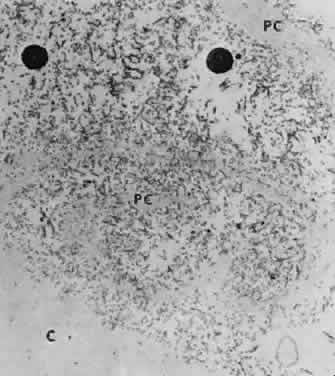

Fig. 11. Transmission electron micrograph of peeling lens capsule (PC) rolled up in spiral, enclosing masses of exfoliative fibers and two melanin granules. C, main capsule (× 14,600). (Courtesy of Dr. Barbara Streeten)